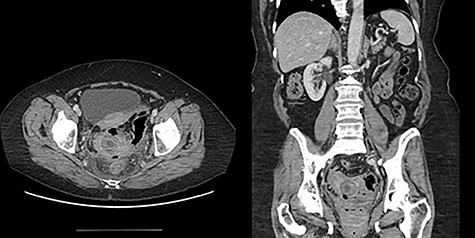

The first patient is a 77-year-old female who presented to the emergency room with a 5-day history of nausea, vomiting, diarrhea and frequent belching. She had a past medical history significant for two episodes of diverticulitis treated non-operatively. She had never undergone abdominal surgery and she had no prior colonoscopy. She was afebrile and hemodynamically stable on evaluation. Her abdominal exam revealed mild distention without tenderness or peritoneal signs. No palpable masses were present on rectal exam. Her labs were remarkable for a mild leukocytosis of 12.4 thou/cmm. She underwent CT imaging of her abdomen and pelvis with oral contrast, which indicated the presence of a gallstone impacted in the proximal sigmoid colon with no contrast passing beyond this location; associated mild small bowel distention and pneumobilia suggested a cholecystoduodenal fistula (Fig. 1).